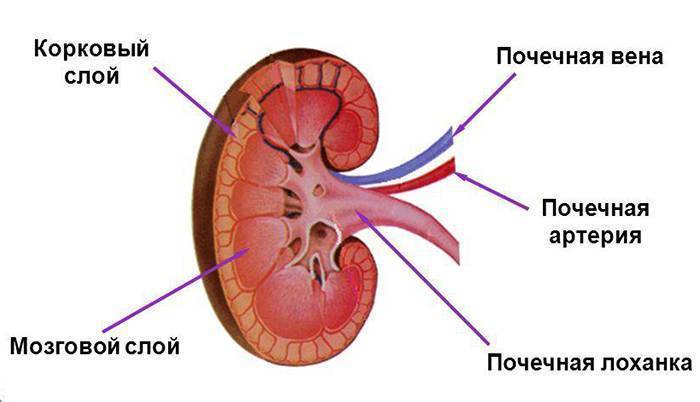

Интраренальная лоханка: рентгеновские снимки и примеры